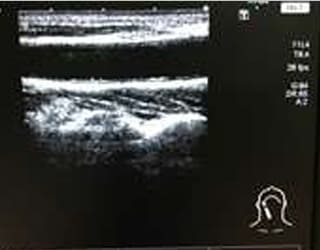

頸動脈エコー

頸動脈エコー検査を用いた頸動脈肥厚度は、早期動脈硬化の標準的指標として、その意義が確立しています。

頸動脈は全身の血管の一部にすぎませんが、そこから連続する脳血管障害との関連や全身の動脈硬化を推定することができます。

特に生活習慣病で治療中の方には、お勧めの検査です。